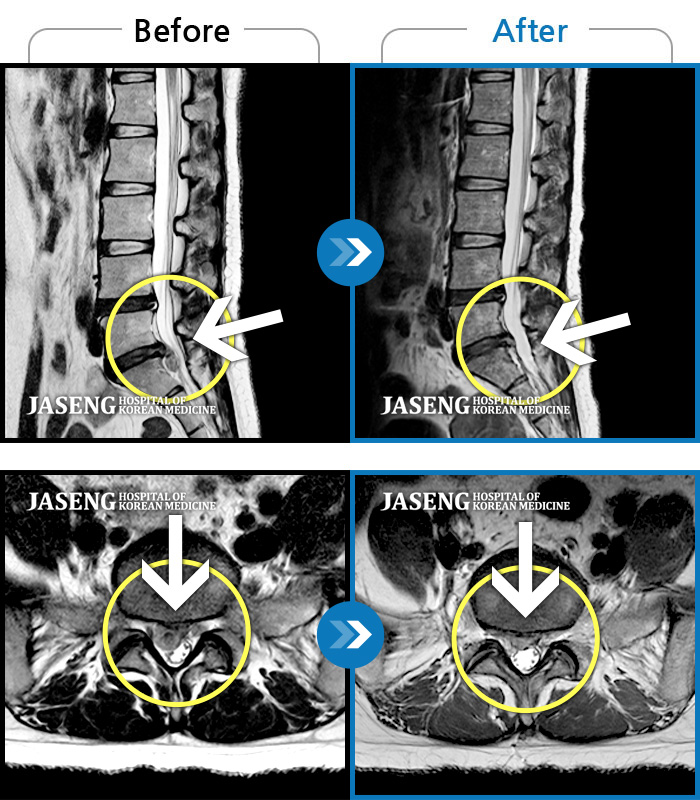

MRI 치료사례

허리디스크

보라매 · 신원준 원장

허리통증과 우측 다리 저림이 심해서 앉거나 서기도 힘들어요

촬영시기

2023.08.01 ~ 2023.11.18